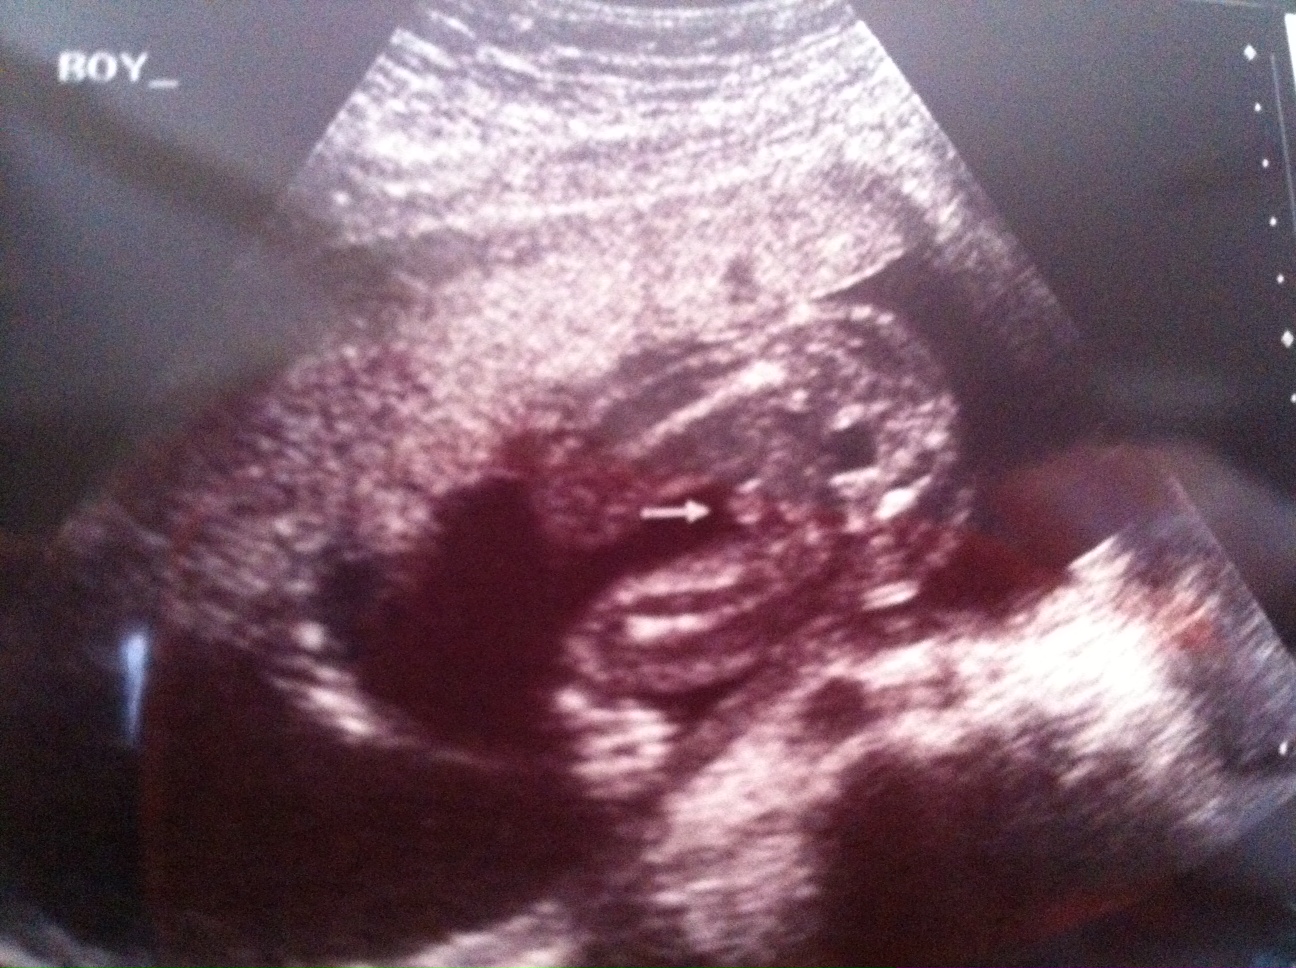

14 week u/s pointed to boy, 20 week u/s leaning towards girl. . . .need another opinion here. :-)

I had a funsies ultrasound in Illinois and was led to believe that my little one was a boy, which fell in line with my thoughts and feelings. However, I had the anatomy scan at 20 weeks and the tech said that she was "pretty sure" then "99.9" sure that it was a little girl.

Although I know that she is good at her job, I just am not feeling it. Yes, I want a 10 finger and 10 toed baby with all body parts in the correct places, but I am just not 100% in agreement with her.

Attachment 12403Attachment 12404Attachment 12403Attachment 12404